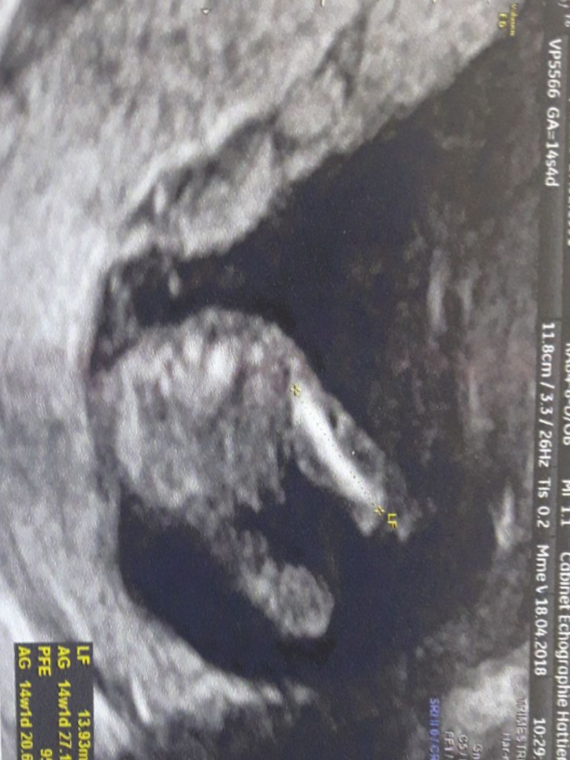

Sentir bebe 14 sa

Ogradica za bebe je idealno mesto za igru Naime, ona ima bezbednu i ravnu površinu, a za razliku od poda, ne postoji opasnost da se beba na bilo koji način udari, povredi ili dođe u kontakt sa nekim vrućim ili opasnim predmetom Kako koristiti ogradicu za bebe Mnogi roditelji se žale da dete ne reaguje blagonaklono kada je spuste u ogradicuE ca o senzatie de fluture care da din aripi 1/La première échographie autour de 12 semaines d'aménorrhée Il est recommandé de la réaliser entre 11 et 14 SA Mais le meilleur moment se situe à 12 ou 13 SA car avant cela, le fœtus n'aura pas atteint une taille suffisante pour le dépistage des signes associés à la trisomie 21 (notamment l'épaisseur de la clarté nucale)

Sentir bebe 14 saのギャラリー